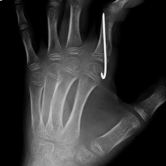

Röntgenbilder